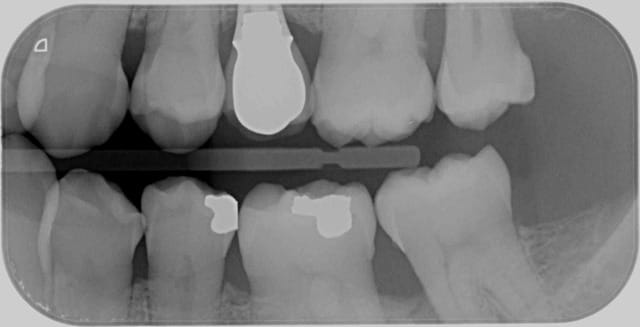

Dans le cas de ce patient j'ai coté HBQK443 car 4 secteurs en tout.

Montre les radios, ce sera plus simple.